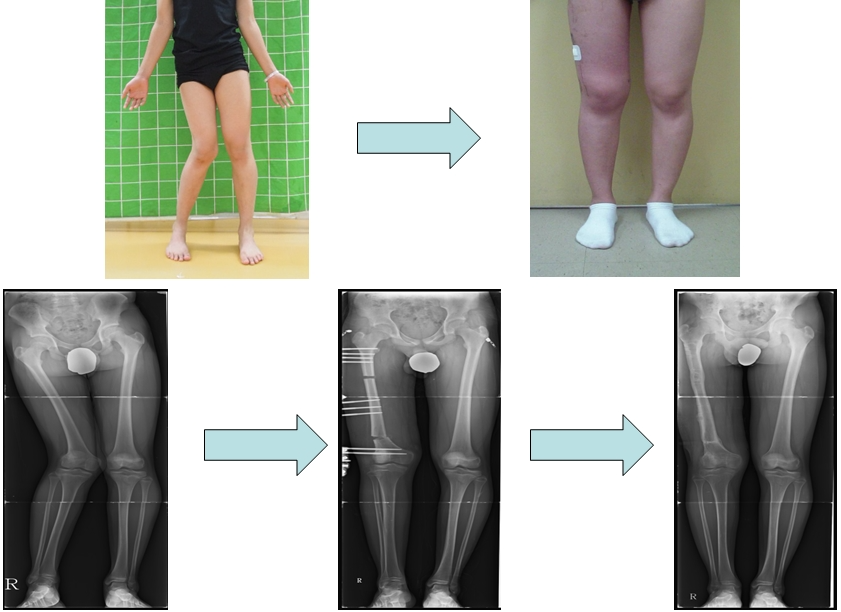

공지 무릎관절손상후 발생한 하지변형에서의 교정관리자2025-10-18 01:10무릎관절 손상 후 한쪽 다리가 밖으로 휘어 허벅지뼈 교정을 받고 일자다리가 되었습니다. Perform correction surgery on femur to correct the valgus deformity of a leg, resulting straightened legs.다음글공지 하지변형에 대한교정이전글공지 소아마비환자의 하지변형에 대한 교정목록